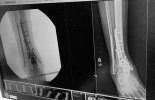

Welp, last month I had one small spot on a gutter screen that had some debris causing some run-over and puddled on my deck. I knew it was gonna freeze and create a hazardous ice sheet. So I got out the ladder and needed to only get up high enough to reach my arm up to the 8' high gutter. I needed to go up one more rung on the ladder to get a better reach and the ladder kick back and out from under me. I came down on my bad ankle from about 6 feet and also rolled back and smacked my head hard on the deck. I knew instantly that my ankle was toast.

Turns out I really did a job on it. When I asked the surgeon if I could lose my foot he didn't exactly say "No". Reading between the lines makes me think that I came close and I am still not out of the woods (so to speak). He stressed many times how serious my injury is, one of the worst he's seen.

Spent a few weeks in the trauma unit with one of those external fixation cages until the swelling went down enough to operate. Left the hospital in a cast and now I'm in a boot...non weight bearing for at least another couple months. Walker and crutches and a knee scooter on the way.

I now have a fuzed ankle, and in me I have more hardware than a piece of modern archery gear.

View attachment 125487